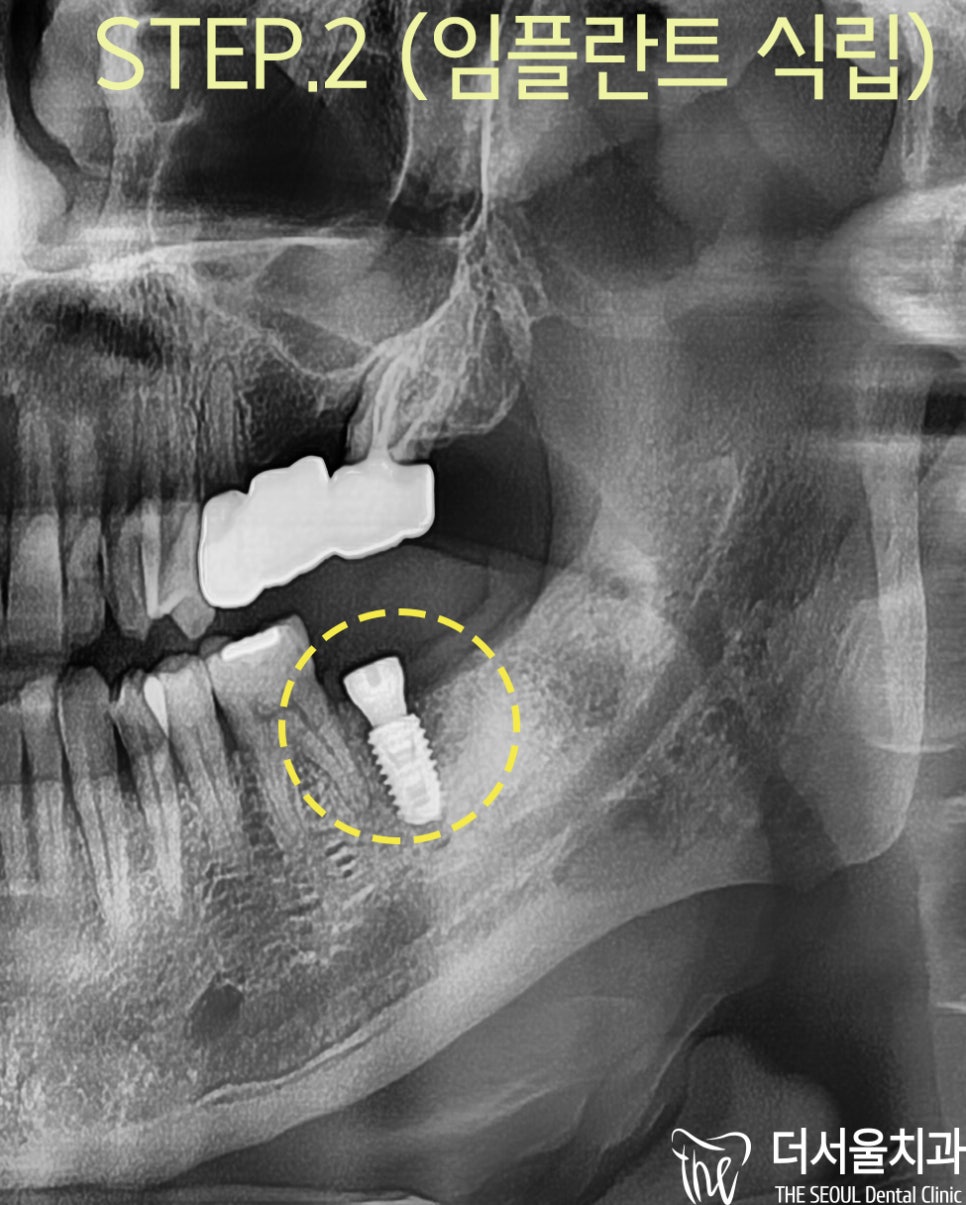

그래서

픽스쳐를 식립하면서

염증을 긁어낸 자리에 뼈이식을 진행하게 되었습니다

수술 후

파노라마 사진을 보여드리면

계획했던 부위에 잘 심긴 것을 볼 수 있으며

대략, 3개월간

골융합 기간을 통해서

임플란트 보철을 올려드릴 수 있었습니다.